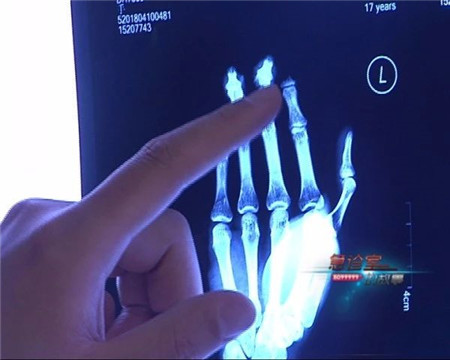

只见小伙右手除大拇指外的四个指头严重受伤,参差不齐的创口下,神经、骨骼几乎被搅碎,X光片显示之下,伤口触目惊心。

这名小伙子姓李,是一名木匠学徒,由于工作中操作不慎,手指被机器紧紧咬住。经过医生诊断,小李手指伤情严重,必须马上实施断指再接手术,且要在有限时间内进行,一旦错过了时机,就有可能影响手指成活率。

云南骨科医院手足(显微)外科 主治医生 曹学新:他伤了四个手指,小伙子挺年轻的,17岁,我们现在尽量想办法,给他把这四个手指都保全了。